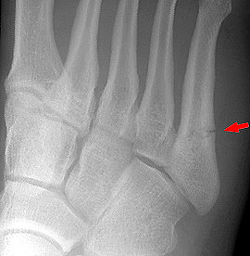

Большинство переломов плюсневых костей является результатом прямого сдавления, например при падении тяжелого предмета на ногу. Непрямой механизм, заключающийся в скручивании переднего отдела стопы, часто приводит к перелому основания V плюсневой кости. Подошвенное сгибание и инверсия напрягают сухожилие короткой малоберцовой мышцы и могут вызвать отрыв шиловидного отростка или бугра у основания V плюсневой кости. Если первоначальным (исходным) механизмом является инверсия, типичен поперечный перелом шиловидного отростка без смещения.

Для выявления этих переломов обычно достаточно снимков в прямой, боковой и косой проекциях. Часто они сопровождаются тыльной угловой деформацией вследствие тяги внутренних мышц. Наличие везалиевой кости (вторичный центр окостенения) у основания V плюсневой кости можно спутать с переломом. Вторичные центры окостенения, как правило, гладкие, закругленные и наблюдаются с двух сторон; часто они имеют склерозированные края. Сначала стрессовые переломы рентгенологически могут не определяться. Однако через 2—3 нед линия перелома обычно становится заметной, а через 4 нед выявляется костная мозоль.

Отрывной перелом класса В у основания V плюсневой кости без смещения требует наложения давящей повязки с нагрузкой на конечность по мере переносимости. Больным с сильными болями может помочь ношение короткого гипсового сапожка в течение 3 нед. Затем показано ношение супинатора для поддержки свода стопы. Следует быть внимательным, чтобы не спутать поперечный перелом проксимального отдела диафиза V плюсневой кости с переломом Джонса, проходящим через ее бугристость. Поперечные переломы, располагающиеся выше бугристости, имеют совсем иной прогноз и лечение. При них наблюдается высокая частота замедленного сращения и несращения.

Аксиома: поперечный перелом основания V плюсневой кости не следует путать с переломом Джонса, проходящим через ее бугристость. Лечение и прогноз для этих переломов различные.

Плюсневые кости входят в группу мелких трубчатых костей скелета человека. Переломы плюсневых костей являются наиболее распространенным переломами костей стопы. А именно переломы основания пятой плюсневой кости, происходящие в результате инверсии стопы. Локализация перелома должна быть тщательно проанализирована врачом, так как лечение различных по локализации и характеру переломов достаточно сильно разнятся.